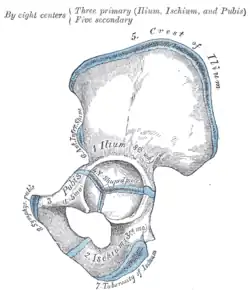

Plan of ossification of the hip bone

Plan of ossification of the hip bone -